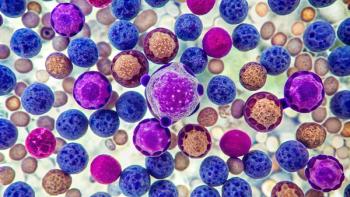

Updated results from a phase 1 study showed that KLN-1010 produced reduced MRD-negative responses in all treated patients with RRMM.

Final results from the CEPHEUS trial showed that daratumumab plus VRd produced deeper, more durable responses and prolonged survival.

DREAMM-9 shows belantamab mafodotin in TI NDMM delivers high responses, with longer dosing improving eye safety and quality of life.